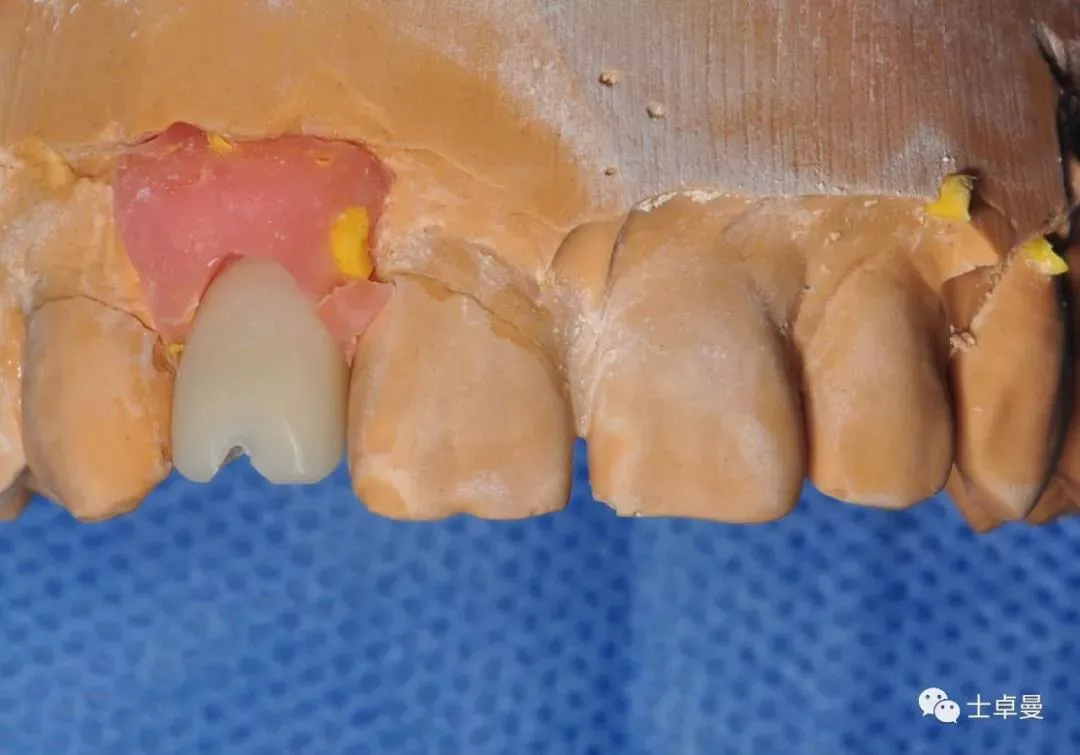

修复操作

修复体制作完成

个性化氧化锆基台

口外预粘结